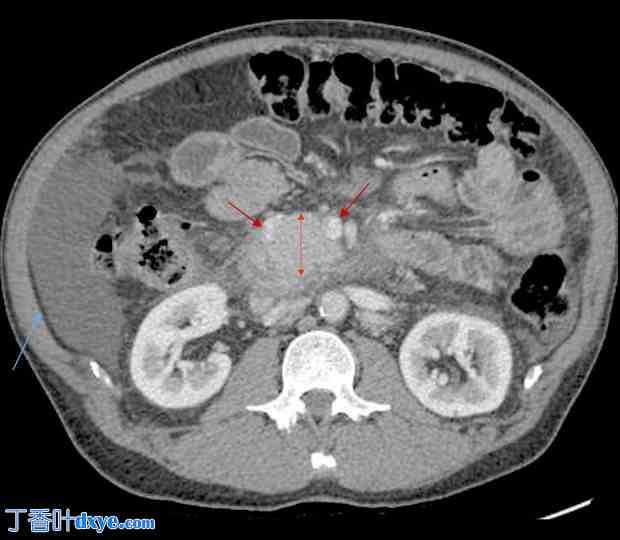

患者短期内病情相对稳定。入院前3个月,腹部CT扫描显示胰头新发肿块(图1、图2)。胰头和胰体部肿大压迫门静脉,导致近端脾静脉高度狭窄。主胰管和胆总管均扩张。肝脏中叶出现新的、边界不清的异质性低密度影,食管和胃内可见多处静脉曲张,提示门静脉充血。肠系膜淋巴结肿大,并伴有炎症改变。胰头肿块的细针穿刺活检结果送病理检查,结果为良性。当时,患者要求进行外科手术以修复疝气

图1.

1.jpg

腹部CT扫描显示胰头巨大肿块(红色箭头)。上腹部可见适量游离液体(蓝色箭头)。